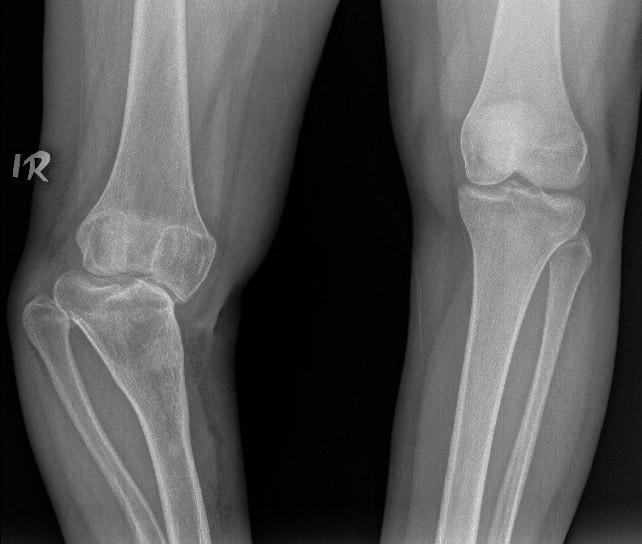

Angular Deformities: Bones bend at abnormal angles, like bow legs or knock knees.

Post-Traumatic Deformities: Resulting from fractures that healed incorrectly.

X-rays: To see bone shape and angles

Osteotomy: Cutting and realigning bones